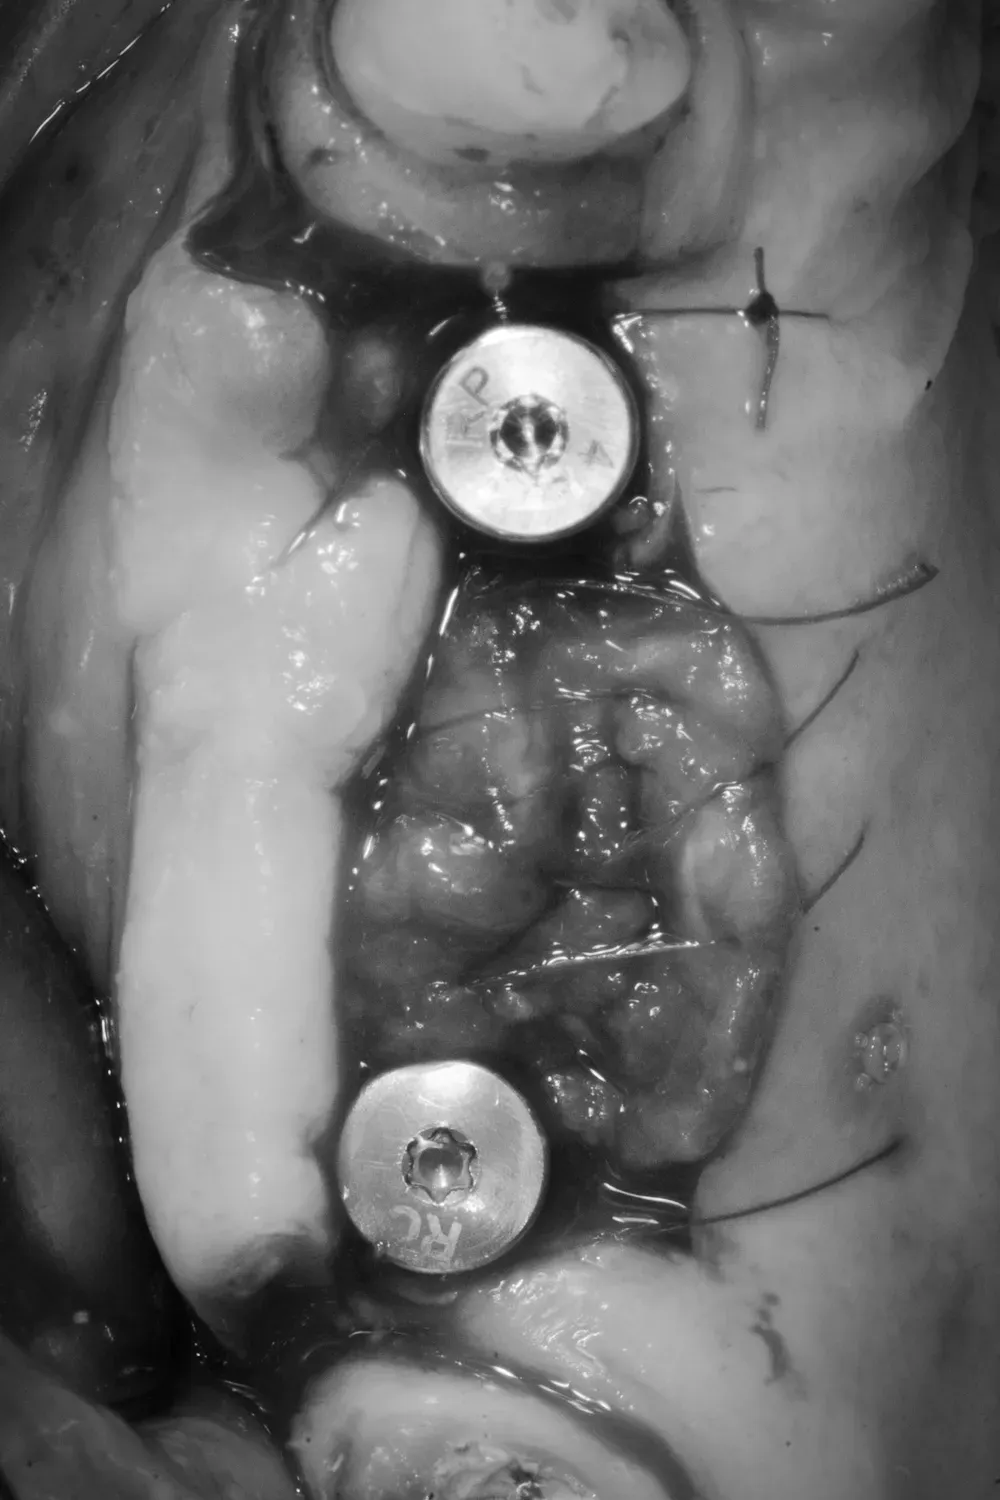

Di seguito potete vedere le foto intra-operatorie posteriori di destra e di sinistra:

Il mascellare superiore destro era affetto da atrofia categoria S3 CCARD in posizione 16 e S2 CCARD in posizione 14 (precedentemente estratto), con presenza di cisti da ritenzione mucosa e setto di Underwood.

Inserimento impianti con rialzo del seno e aspirazione cisti da ritenzione mucosa del seno mascellare

Ho inserito due impianti, in posizione appunto 16 e 14, con minirialzo del seno mascellare e aspirazione della cisti da ritenzione mucosa tramite accesso laterale.